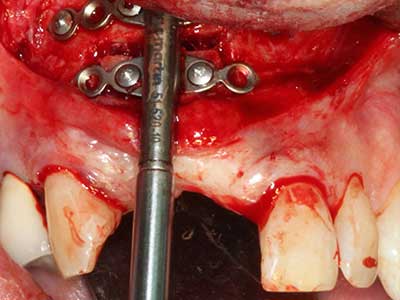

Abb. 18: Präparation eines Kortikalis-Deckels mit der Piezo-Knochensäge (Piezomed, W&H).

Abb. 19: Operationssitus nach Neurolyse und Osteomentfernung.